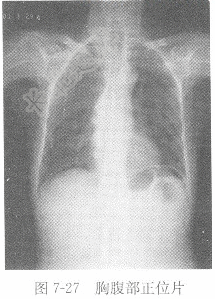

试题详情单项选择题男性,50岁,上腹痛10h,腹部平片见图7-27,X线诊断为( )。A、消化道穿孔B、肺炎C、正常胸片D、气胸正确答案:关注下方微信公众号,搜题查看答案热门试题葡萄糖耐量试验心脏大动脉血氧分压(PaO2)窦性心动过速检查骨髓常规检查血清钠参考值血、尿淀粉酶(AMS)粪常规胃、十二指肠溃疡肺炎血浆凝血酶原时间(PT)肌酸激酶(CK)癌胚抗原(CEA)CT检查X线片男性,56岁,上腹痛半年,胃肠道造影图像男性,73岁,痰中带血2周,X线影像见图二氧化碳结合力(CO2CP)肠结核血清碱性磷酸酶(ALP)